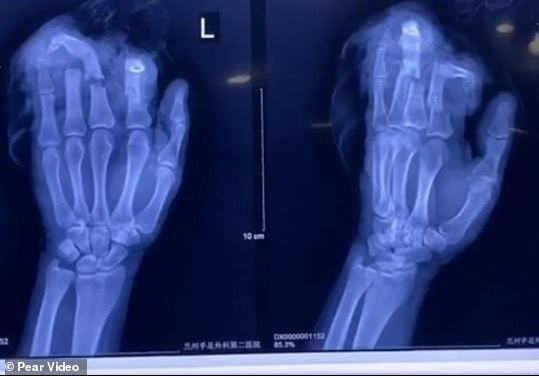

‘The patient’s left index, middle, ring and little fingers were completely severed. There was seriously damage to the bone,’ a doctor at the Lanzhou Hand & Foot Surgical Hospital told reporters on Friday.

The doctor added that the man would not be able to attain 100 per cent of normal motion from his reattached fingers. ‘We performed emergency surgery and successfully reattach his fingers, but permanent partial loss of function is inevitable in the future,’ he added.